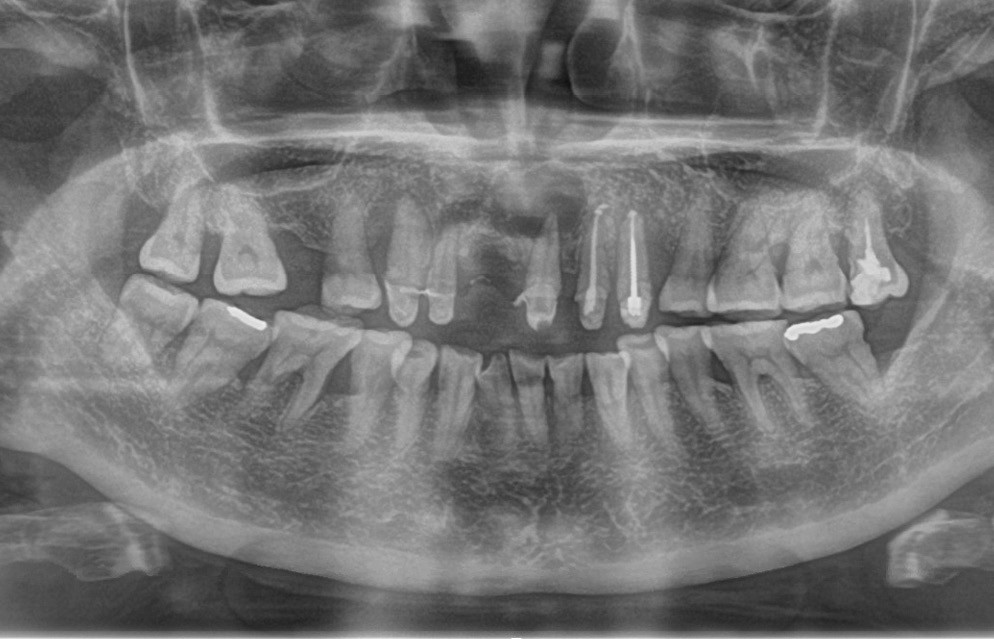

Le kyste radiculo-dentaire (fig. 1 et 2), également retrouvé sous le terme de kyste apico-dentaire, ou radiculaire, est le plus fréquent des kystes des maxillaires [1]. Il s’intègre dans la grande famille des tumeurs bénignes osseuses odontogéniques et maxillo-faciales (classification internationale de l’OMS, 2017). Il se développe aux dépens d’un granulome péri-apical secondaire à une nécrose dentaire. Le mécanisme physiopathologique à l’origine de la formation kystique est la prolifération de débris épithéliaux (débris de Malassez) présents dans le desmodonte sous l’action de stimuli inflammatoires. Un kyste est constitué d’une membrane épithéliale et d’une cavité plus ou moins liquidienne, voire solide dans certains cas. On y retrouve des cristaux de cholestérol, des calcifications dystrophiques d’exsudat inflammatoire, des macrophages, des plasmocytes, des cellules ciliées, muqueuses, géantes multinuclées et, dans certains cas, des globules rouges.

On distingue classiquement le granulome (- 1 cm) du kyste (+ 1 cm). Ce dernier possède des parois propres et des contours réguliers bien délimités. Le développement kystique s’accompagne volontiers d’un refoulement des structures avoisinantes, les corticales osseuses apparaissent soufflées, dans certains cas, amincies, pouvant venir empiéter sur des éléments anatomiques de la sphère maxillo-mandibulaire (sinus, canal mandibulaire, fosses nasales, foramen mentonnier…) (fig. 3).